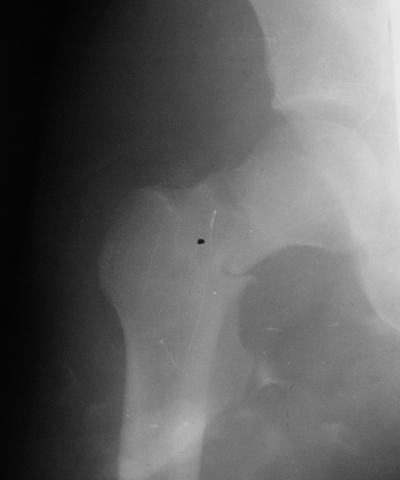

Лечился в стержневом аппарате по месту жительства. АВФ демонтировали через полгода из-за воспаления в области стержней (рис 2). После демонтажа в течение месяца больной лихорадил до 38*, были боли в бедре. Эти явления исчезли после курса антибиотиков. Через год после травмы в ЦРБ ему имплантировали биполярный протез (рис 3). Рана зажила первично. Ходил с костылями, слегка приступая на ногу. На контрольных осмотрах выявлена прогрессирующая протрузия (рис 4-6).